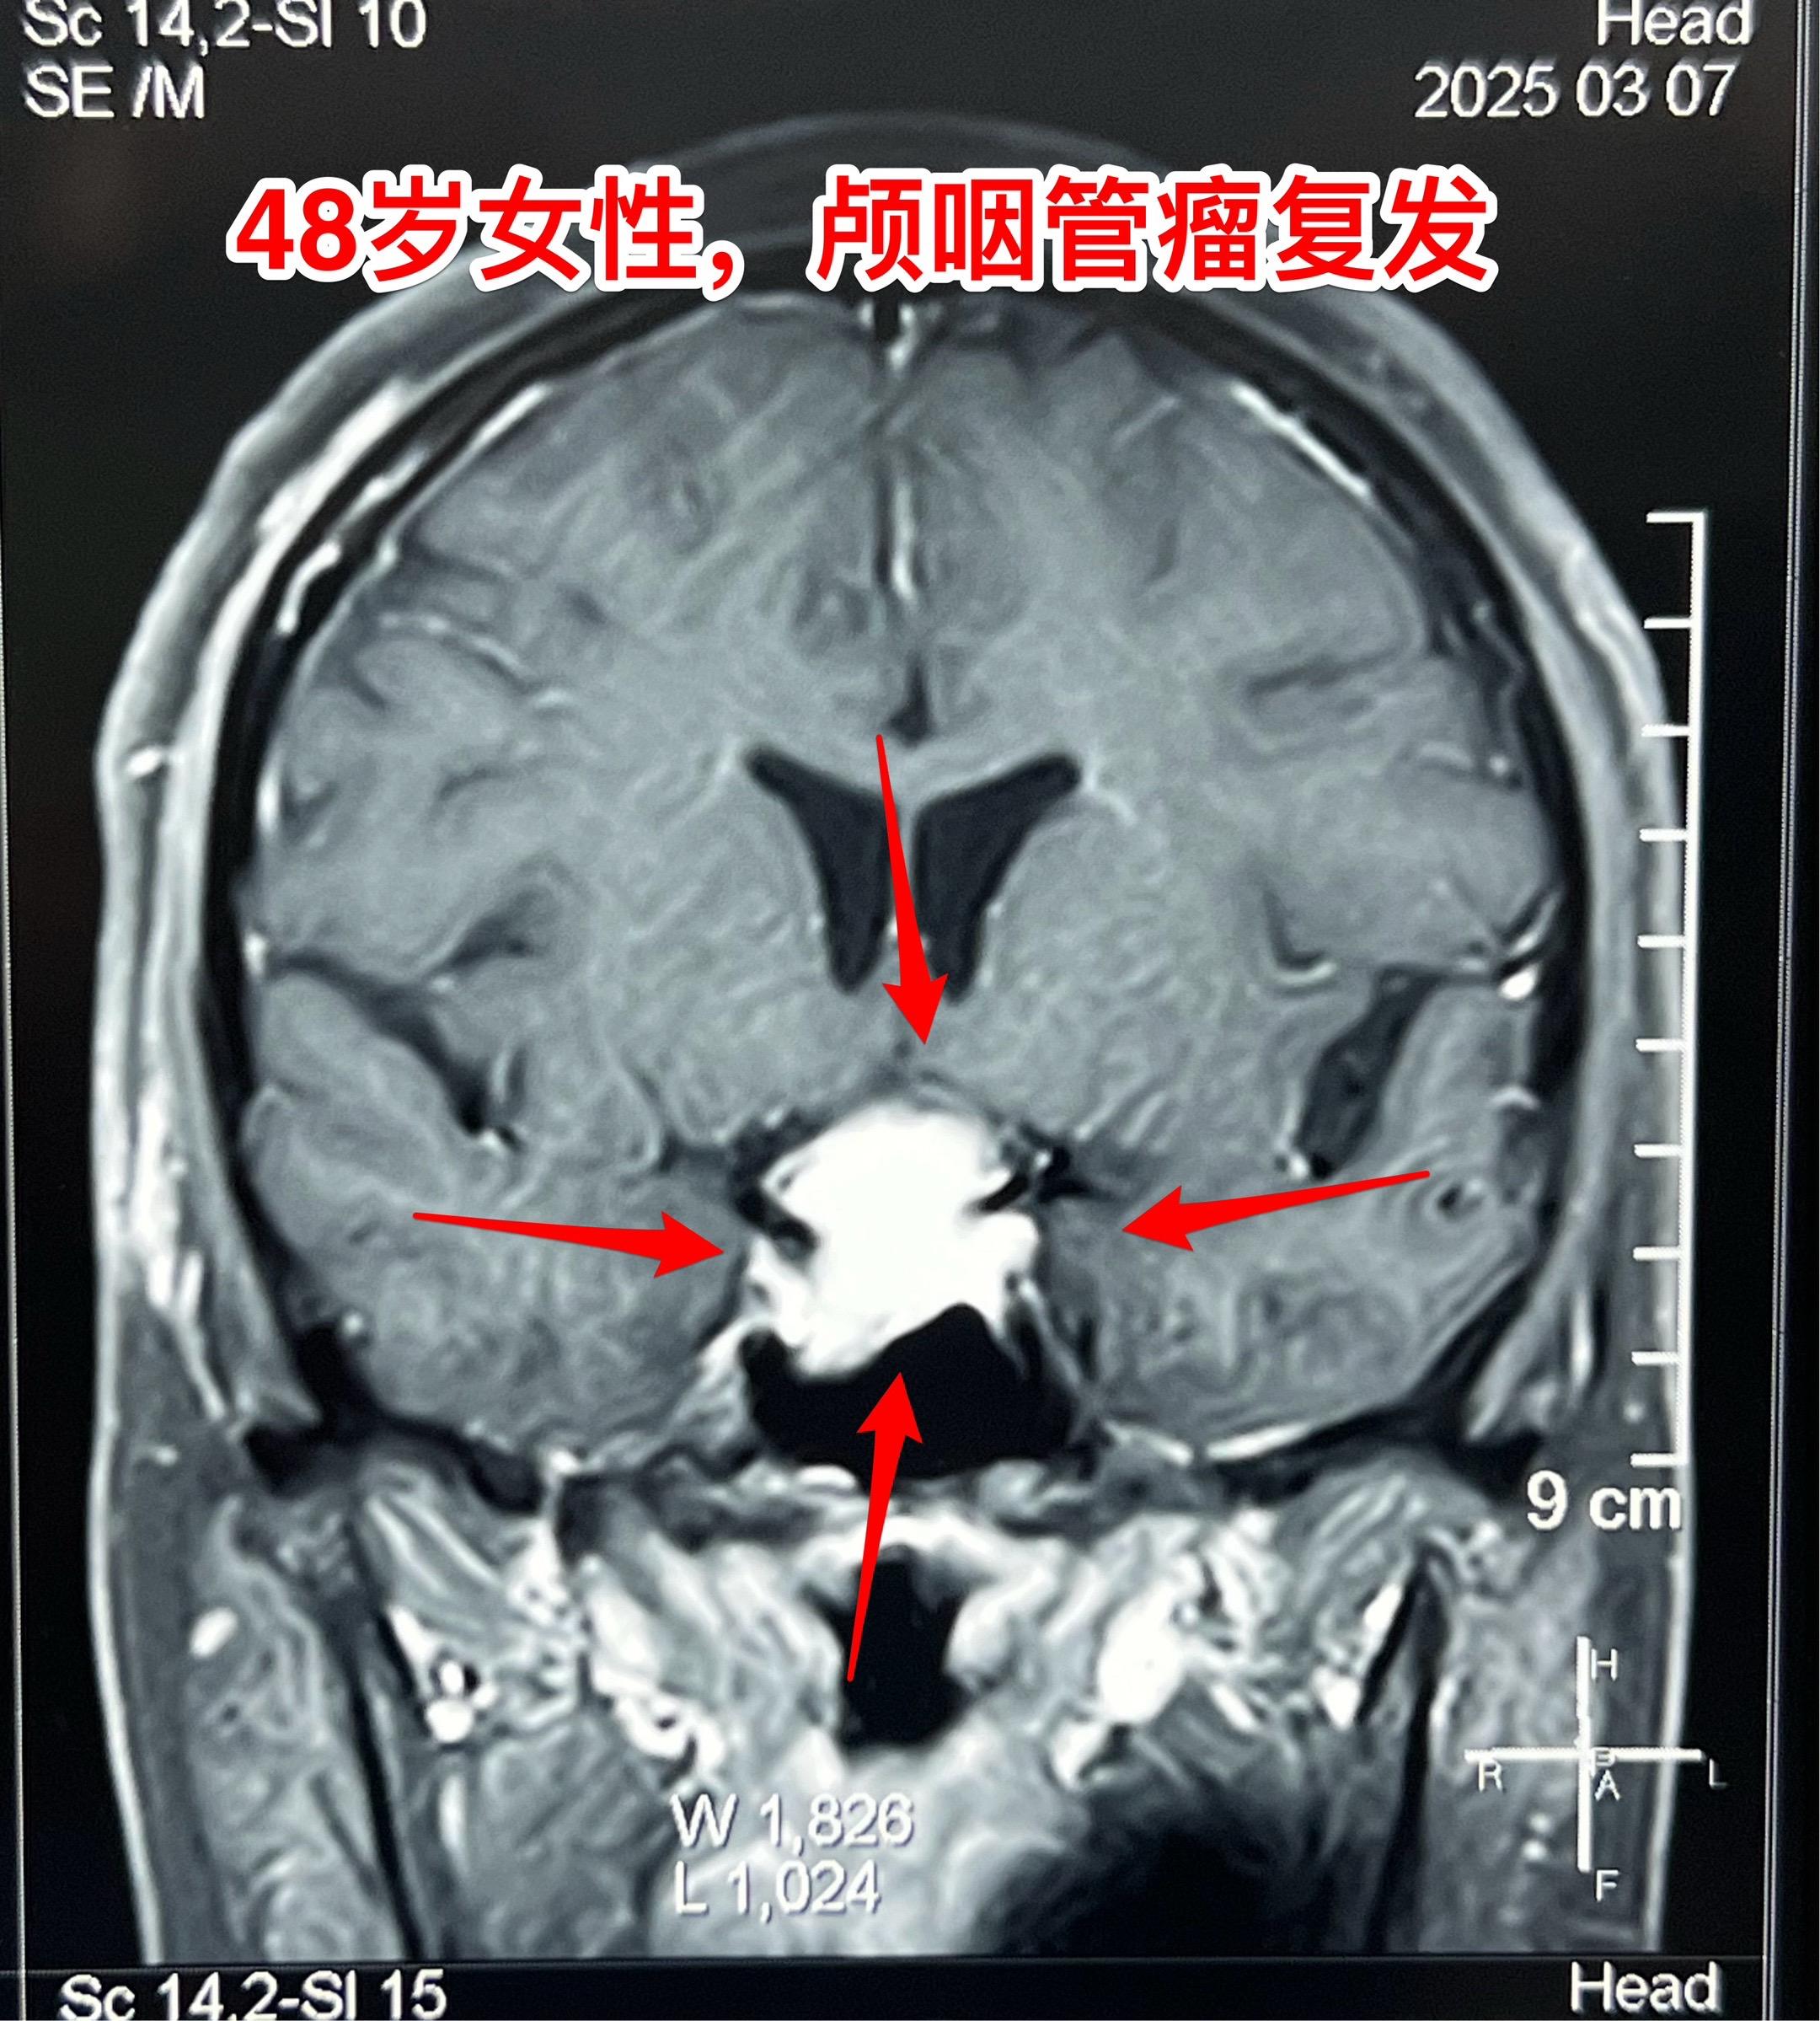

今天的第二个颅咽管瘤手术。48岁女性,洛阳市人。因颅咽管瘤先后行经鼻手术和开颅手术各一次。开颅手术是在24年12月作的,手术后又出现右眼视力下降,复查磁共振显示肿瘤复发,见图。 这个肿瘤看起来似乎难度不大,其实不然。距离前一次手术刚刚三个月,瘢痕粘连紧密而且肿瘤向左右两侧均嵌入视神经-颈内动脉缝隙内。这是乳头型颅咽管瘤,很有难度!